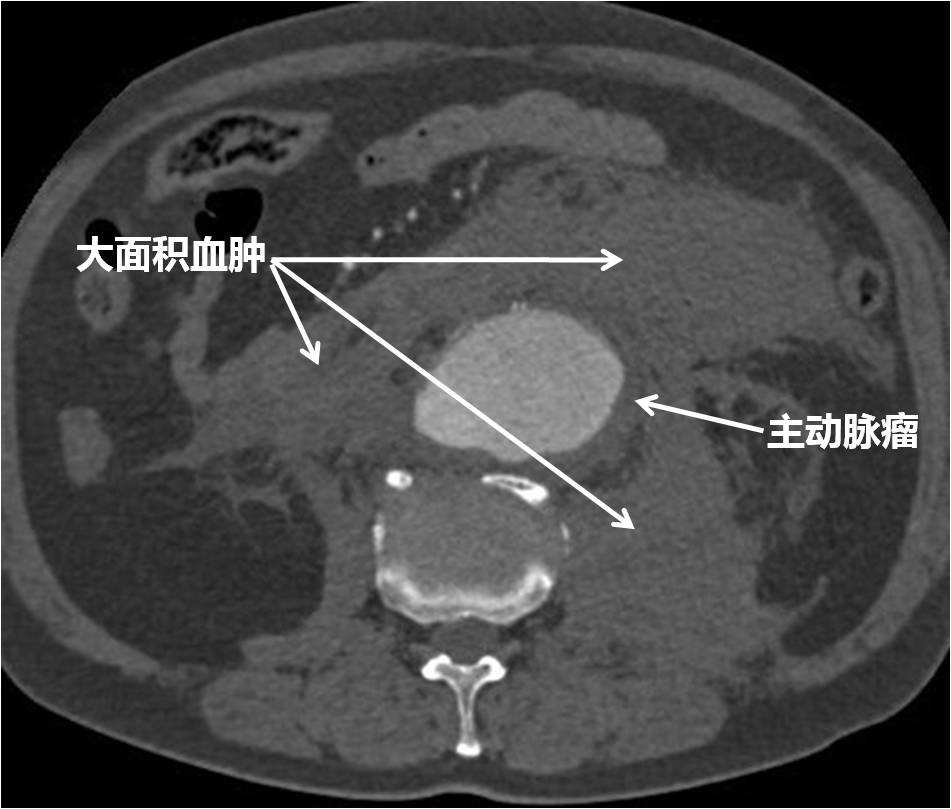

介入血管外科成功抢救一例破裂性腹主动脉瘤合并休克患者

近日,北医三院介入血管外科在急诊科、麻醉科、手术室、泌尿外科、放射科和输血科等科室的大力协助下,成功将一位76岁的破裂性腹主动脉瘤合并失血性休克的危重患者从死亡线上抢救回来。 2018年2月25日,是春节假期结...